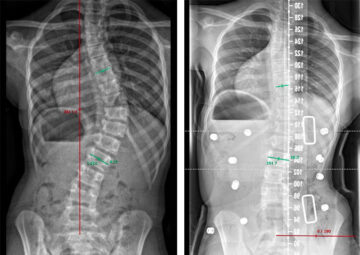

فعالية حزام اعوجاج العمود الفقري: كيف يقلل الأنحناء ويحقق نتائج ملموسة يعاني العديد من الأطفال والمراهقين من الجنف مجهول السبب (Adolescent Idiopathic Scoliosis)، وهي حالة يتميز فيها العمود الفقري بانحناء جانبي غير طبيعي. ويُعد

هل يحدد مقدار التصحيح داخل حزام اعوجاج العمود الفقري نجاح العلاج لطفلك؟ يعتمد نجاح علاج اعوجاج العمود الفقري مجهول السبب عند المراهقين بشكل كبير على العلاج بالحزام الطبي، لكن كثيرًا من الأهل يسألون: ما

تأثير معدل شدة الاعوجاج على نجاح حزام اعوجاج العمود الفقري؟ يعاني العديد من المراهقين من اعوجاج العمود الفقري (الجنف)، وهو انحناء جانبي للعمود الفقري يمكن أن يتفاقم مع النمو السريع خلال فترة المراهقة. من